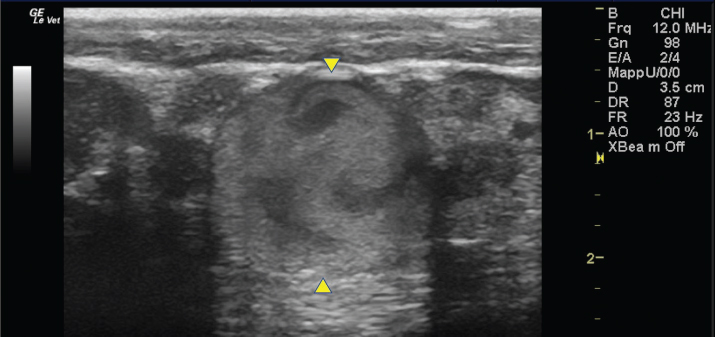

Fig. 2. A 20-G intravenous catheter placed into the right congestive facial vein in the anesthetized horse. The left jugular vein appeared as an anechoic tubular structure which collapsed under the probe pressure, the color Doppler examination revealed normal blood flow within the vessel (Fig. 3). Bi-dimensional ultrasonography of the right jugular vein showed a heterogeneous, non-cavitating, hypoechoic structure occluding a narrowed right jugular vein for about 30 cm of length localized in the proximal and mid-portion of the neck compatible with a thrombus (Fig. 4). The color Doppler examination showed blood flow through the lateral portions of the thrombus in the cranial and mid-portions of the right jugular vein (Fig. 5). Cranially to the thrombus, a marked distension of the maxillary and linguofacial veins was evident, with a turbulent and echogenic flow; the latter was compatible with blood stasis near the thrombus (Fig. 6). Caudally to the thrombus, the right jugular vein presented reduced diameter, thickened walls, and normal blood flow (Fig. 7). The cranial part of the thrombus originated from a heterogeneous scare tissue, localized at the level of the right mandibular angle (Fig. 8). After injection of the first saline contrast bolus in a right facial vein, no microbubbles appeared in the right jugular vein, caudally to the thrombus, proving the presence of a complete right jugular vein occlusion. On the contrary, after injection of the second bolus, microbubbles were visualized in the left jugular vein as small, intense, echo signals within the vein lumen, demonstrating the presence of collateral circulation that drained the blood from the right facial veins to the left jugular vein (Fig. 9). Venography results confirmed the complete occlusion of the right jugular vein and the presence of submandibular venous collaterals that connected the right facial veins with the left jugular vein (Figs. 10 and 11). Based on the previous results, the diagnosis of JVT with complete occlusion of the vessel lumen was confirmed. The horse’s owner refused any proposed medical or surgical therapy.

Fig. 6. Bi-dimensional ultrasonographic image of the dilated right maxillary vein (between arrowheads). Note the turbulent and echogenic flow compatible with blood stasis near the thrombus.